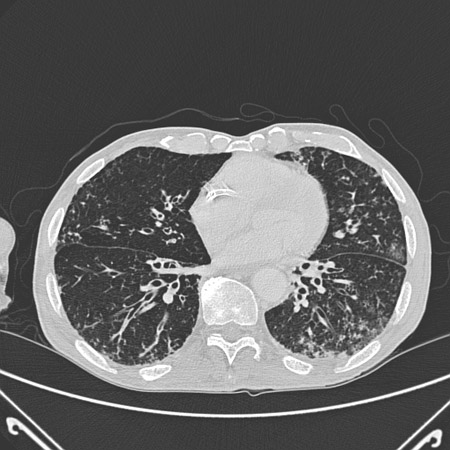

[Figure caption and citation for the preceding image starts]: Tomografia computadorizada (TC) do tórax com presença de anel de sinete à esquerda em paciente com bronquiectasiaDo acervo pessoal da Dra. S.M. Bhorade, University of Chicago Medical Center [Citation ends].

[Figure caption and citation for the preceding image starts]: Tomografia computadorizada (TC) do tórax com vias aéreas dilatadas e espessadas e um padrão de árvore em brotamento periférico em paciente com bronquiectasiaDo acervo pessoal da Dra. S.M. Bhorade, University of Chicago Medical Center; usado com permissão [Citation ends].